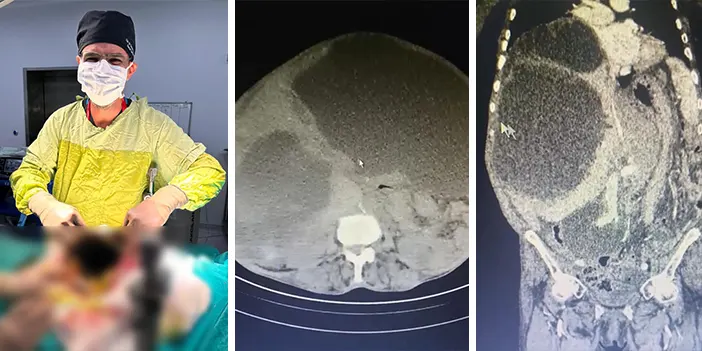

Genel Cerrahi Uzmanı Opr. Dr. İsmet Çelik, Gastroenteroloji Uzmanı Doç. Dr. Aydın Aktaş ve ekibi tarafından yapılan operasyonda 76 yaşındaki Asiye Taşdelen'in karaciğerinde toplamda 90 santimetreye ulaşan 3 ayrı kedi-köpek kisti ameliyatla çıkartıldı.

Kistlerin büyüklüğü dikkat çekerken Genel Cerrahi Uzmanı Opr. Dr. İsmet Çelik, dünya literatüründe tüm karnı dolduran ve 90 santime ulaşan kist görmediklerini belirterek Taşdelen'e yapılan gerekli tetkikler ve görüntüleme sonucu karaciğerinde üç adet kedi-köpek kisti (hidatik kist) tespit ettiklerini ifade etti. Çelik, başarılı geçen ameliyatın ardından hastanın sağlık durumunun iyi olduğunu ve sürecin yakından takip edildiğini belirtti.

Dünya literatüründe tüm karnı dolduran ve 90 santime ulaşan kist görmediklerini ifade eden Çelik, "Asiye Hanım, maalesef ihmal edilmiş bir hastamız. Bu kist, kedi ve köpeklerin dışkısı ve yediği yiyeceklerle bulaşan bir hastalık. Bu kist, genellikle tesadüfen yakalanabilir. Karaciğere yerleşir. Bu hastamızda da durum öyle olmuş. Ameliyat olamayacağı söylenip eve yollanmış. Bizler detaylandırıp ameliyat kararı aldık. Hastamızın karaciğerinde 3 ayrı kist vardı. Tüm karnı kist ile kaplıydı. 2 tanesinin tamamına çıkardık. Diğerini ise kontrolle alarak içini boşalttık.

Dünya literatüründe tüm karnı dolduran ve 90 santime ulaşan kist görmedik. Ameliyatımız 2 saat sürdü. Hastamızın safra yolları kontrol edildi. Hastamızın durumu gayet iyi. Solunum cihazından bağımsız olarak kendi başına solunum yapabiliyor. En korktuğumuz şey; alerjik bir durumun olması. 90 santim çapındaki kist vücuda yayıldığı zaman alerjik bir durumda hastanın ölümüne sebep olabilmesi. Göremediğimiz yayılımlar için tedbir alıyoruz" diye konuştu.